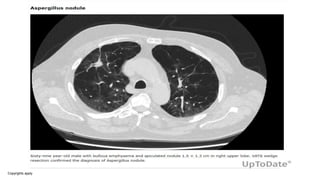

Aspergillus nodule

• One or more nodules (<3 cm), which do not usually cavitate, an

unusual form of CPA. It may mimic carcinoma of the lung,

metastases, cryptococcal nodule, coccidioidomycosis or other rare

pathogens and can only be definitively diagnosed on histology.

• Nodules in patients with rheumatoid arthritis may be pure rheumatoid

nodules or contain Aspergillus. Tissue invasion is not demonstrated,

although necrosis is frequent. Sometimes lesions larger than 3 cm in

diameter are seen and may have a necrotic centre. These are not

well described in the literature and are best described as “mass

lesions caused by Aspergillus.

• Patients with Aspergillus nodules are typically asymptomatic

and have undergone a percutaneous or excisional biopsy of a

lung nodule to rule out malignancy. The diagnosis is made

when the biopsied tissue reveals fungal hyphae consistent

with Aspergillus on histology and no other etiology is identified.

• The radiological appearance of an Aspergillus nodule cannot be

reliably distinguished from nodules of other etiologies, including

malignancy.

• Patients may have single or multiple Aspergillus nodules.

Successive axial views within the lung window showing Aspergillus nodules, of variable size and borders, and a

fungus ball filling a cavity with a wall of variable thickness in a patient with pre-existing bronchiectasis and

cicatricial atelectasis of the mi...

David W. Denning et al. Eur Respir J 2016;47:45-68

©2016 by European Respiratory Society